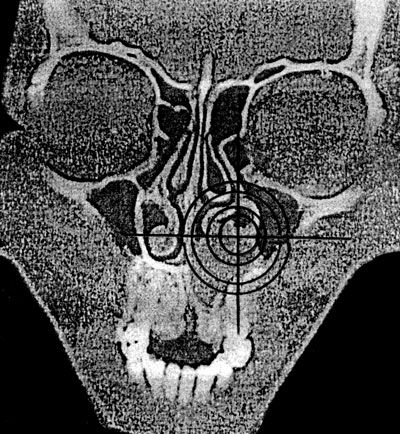

Оценка положения органа или его части может производиться как качественно, так и количественно (глубина залегания органа по кратчайшему расстоянию от поверхности, расчет координат с использованием осей абсцисс и ординат) – рис. 8.

Рис. 8. Определение координат кисты центрального отдела верхней челюсти (срез на уровне премоляров) на компьютерной томограмме (по: Соловьев М. М., Семенов Г. М., Галецкий Д. В., 2004).

Для реализации количественного подхода необходим выбор ориентации плоскости условного сечения и определение точки отсчета. К наиболее простым способам относится определение координат в горизонтальной плоскости с расположением "нулевой" точки в центре тела позвонка. Последовательное изменение угла обзора, а также компьютерное интегрирование (наложение) полученных изображений позволяет составить целостное представление об особенностях топографии анализируемого объекта.